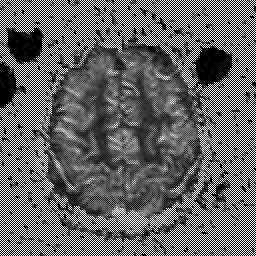

Alzheimer's Disease: SPECT/fMRI overlay -- Slice #8

Keith A. Johnson (keith@bwh.harvard.edu), J. Alex Becker (jabecker@mit.edu)